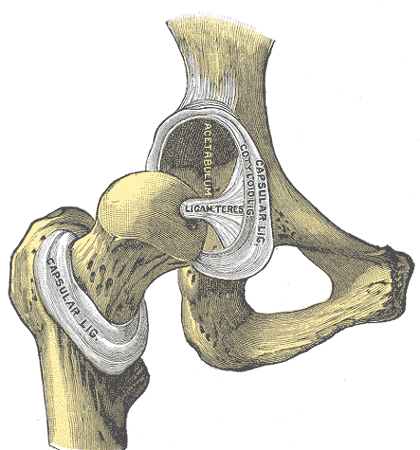

Acetabulum of the os coxae

the socket that holds the femoral head